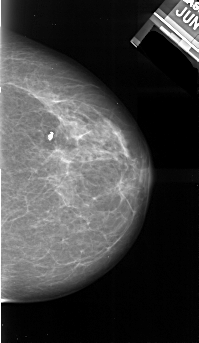

A_1040_1.RIGHT_CC

RIGHT_MLO LINES 5491 PIXELS_PER_LINE 3001 BITS_PER_PIXEL 16 RESOLUTION 42 OVERLAY